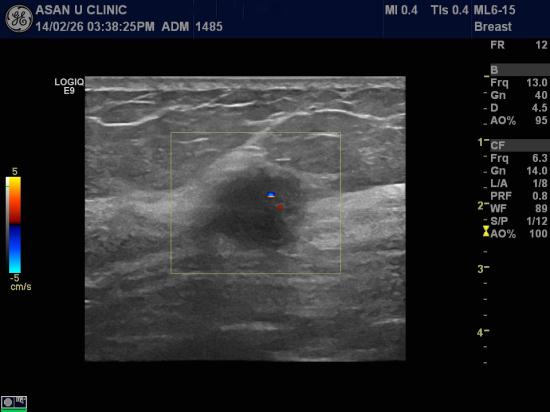

아산유외과 개원 후 68째 유방암진단.

54세 여성분입니다.

건강검진으로 실시한 유방검사에서 이상소견 나와

본원으로 조직검사위해 의뢰되셨습니다.

중심핵생검으로 시행하여

침윤성 유관암 진단되셨습니다.

2cm가 넘는 작지않은 좌측유방의 혹을 왜 모르셨냐는 질문에

건강검진을 규칙적으로 해서 신경쓰지 않으셨다고 하십니다.

건강검진 사이에도

유방에 몽우리가 만져지는 지 꾸준히 촉진해봐야 할 필요가 있습니다.